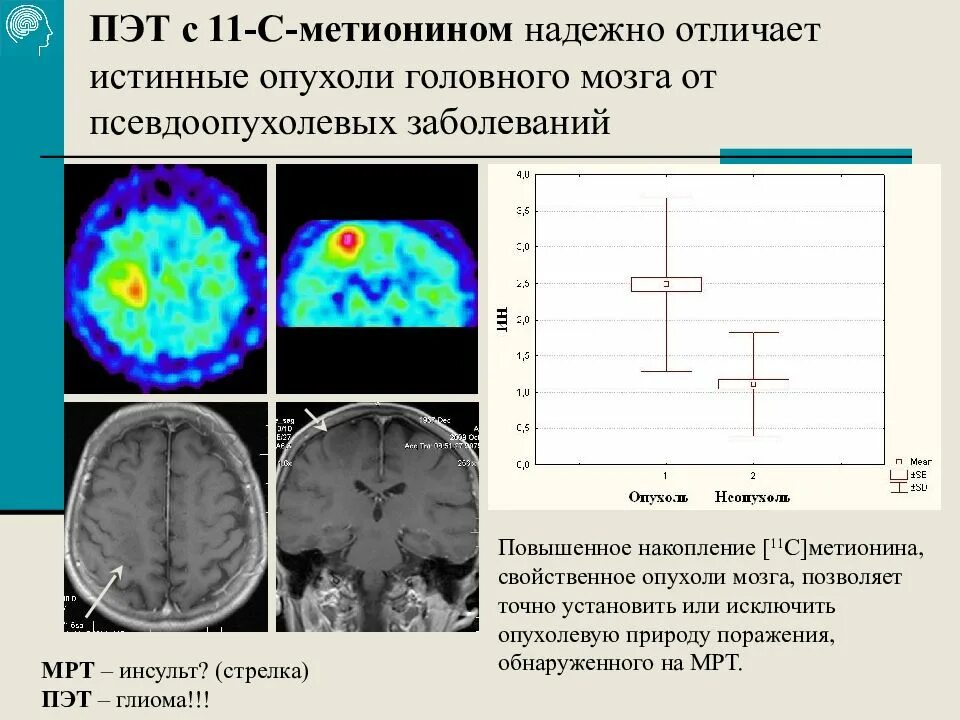

ЭРХПГ при холедохолитиазе заключение. Желчнокаменная болезнь лучевая диагностика. Эндоскопическое исследования механической желтухи. Лучевые исследования при желтухе. Позитронно-эмиссионная томография мозга. ПЭТ кт головного мозга. ПЭТ кт опухоли головного мозга. Позитронно-эмиссионная томография опухоли.

Позитронно-эмиссионная томография мозга. ПЭТ кт головного мозга. ПЭТ кт опухоли головного мозга. Позитронно-эмиссионная томография опухоли. Общие симптомы онкологии. Симптомы онкологических заболеваний. Основные симптомы онкологии. Симптомы раковых заболеваний.

Глиома внутримозговая кт. Метастатические опухоли мозга. ПЭТ кт томограмма. Кт, ПЭТ И ПЭТ/кт. ПЭТ кт с контрастом. Скопление контраста ПЭТ кт.

ПЭТ кт томограмма. Кт, ПЭТ И ПЭТ/кт. ПЭТ кт с контрастом. Скопление контраста ПЭТ кт. Метастатическое поражение печени. Метастатические опухоли печени. Злокачественные образования печени.